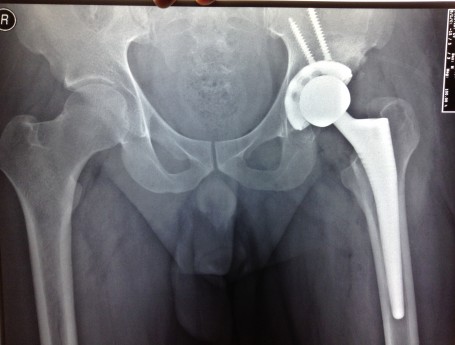

Bilateral Total Hip Arthroplasty Anterior Approach

Revision Total Hip Arthroplasty